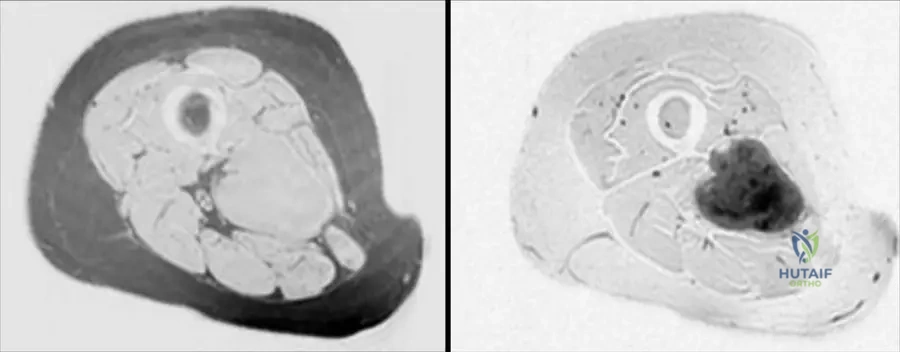

A 63-year-old male presents with a deep-seated mass in his thigh. An MRI is performed to characterize the lesion. The axial T1-weighted image is shown.

Correct Answer: A

Rationale: The clinical context for Fig. 9.19 states: "Axial T1(a) and axial T2-weighted MRI with fat saturation (b) showing typical MRI features of a soft tissue sarcoma with intermediate signal intensity on T1 (isointense with muscle)." Main Distractor: B) Markedly high signal intensity, brighter than fat. This is incorrect; T1 signal for STS is typically intermediate, isointense with muscle, not markedly high like fat.

A 63-year-old male presents with a deep-seated mass in his thigh. An MRI is performed to characterize the lesion. The axial T2-weighted MRI with fat saturation is shown.

Rationale: The clinical context for Fig. 9.19 states: "Axial T1(a) and axial T2-weighted MRI with fat saturation (b) showing typical MRI features of a soft tissue sarcoma with intermediate signal intensity on T1 (isointense with muscle) and markedly heterogeneous predominantly high signal intensity on T2." Main Distractor: B) Homogeneous low signal intensity. This is incorrect; sarcomas typically show high signal on T2, and often with heterogeneity, not homogeneous low signal.

Rationale: The clinical context for Fig. 9.19 states: "Note that the tumor originates within the deep muscular compartment of the thigh." Main Distractor: B) Subcutaneous compartment. While some sarcomas are subcutaneous, the text specifically states this particular tumor (Fig 9.19) originates in the "deep muscular compartment."